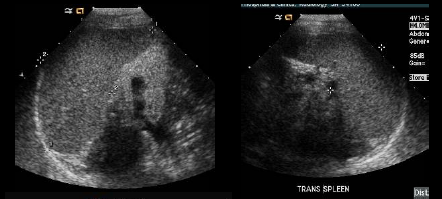

what plane was this image taken in?

transverse

which plane are each of these spleens in? how can you tell?

lt long, rt trans

look for the hilum.